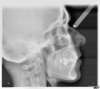

Téléradio